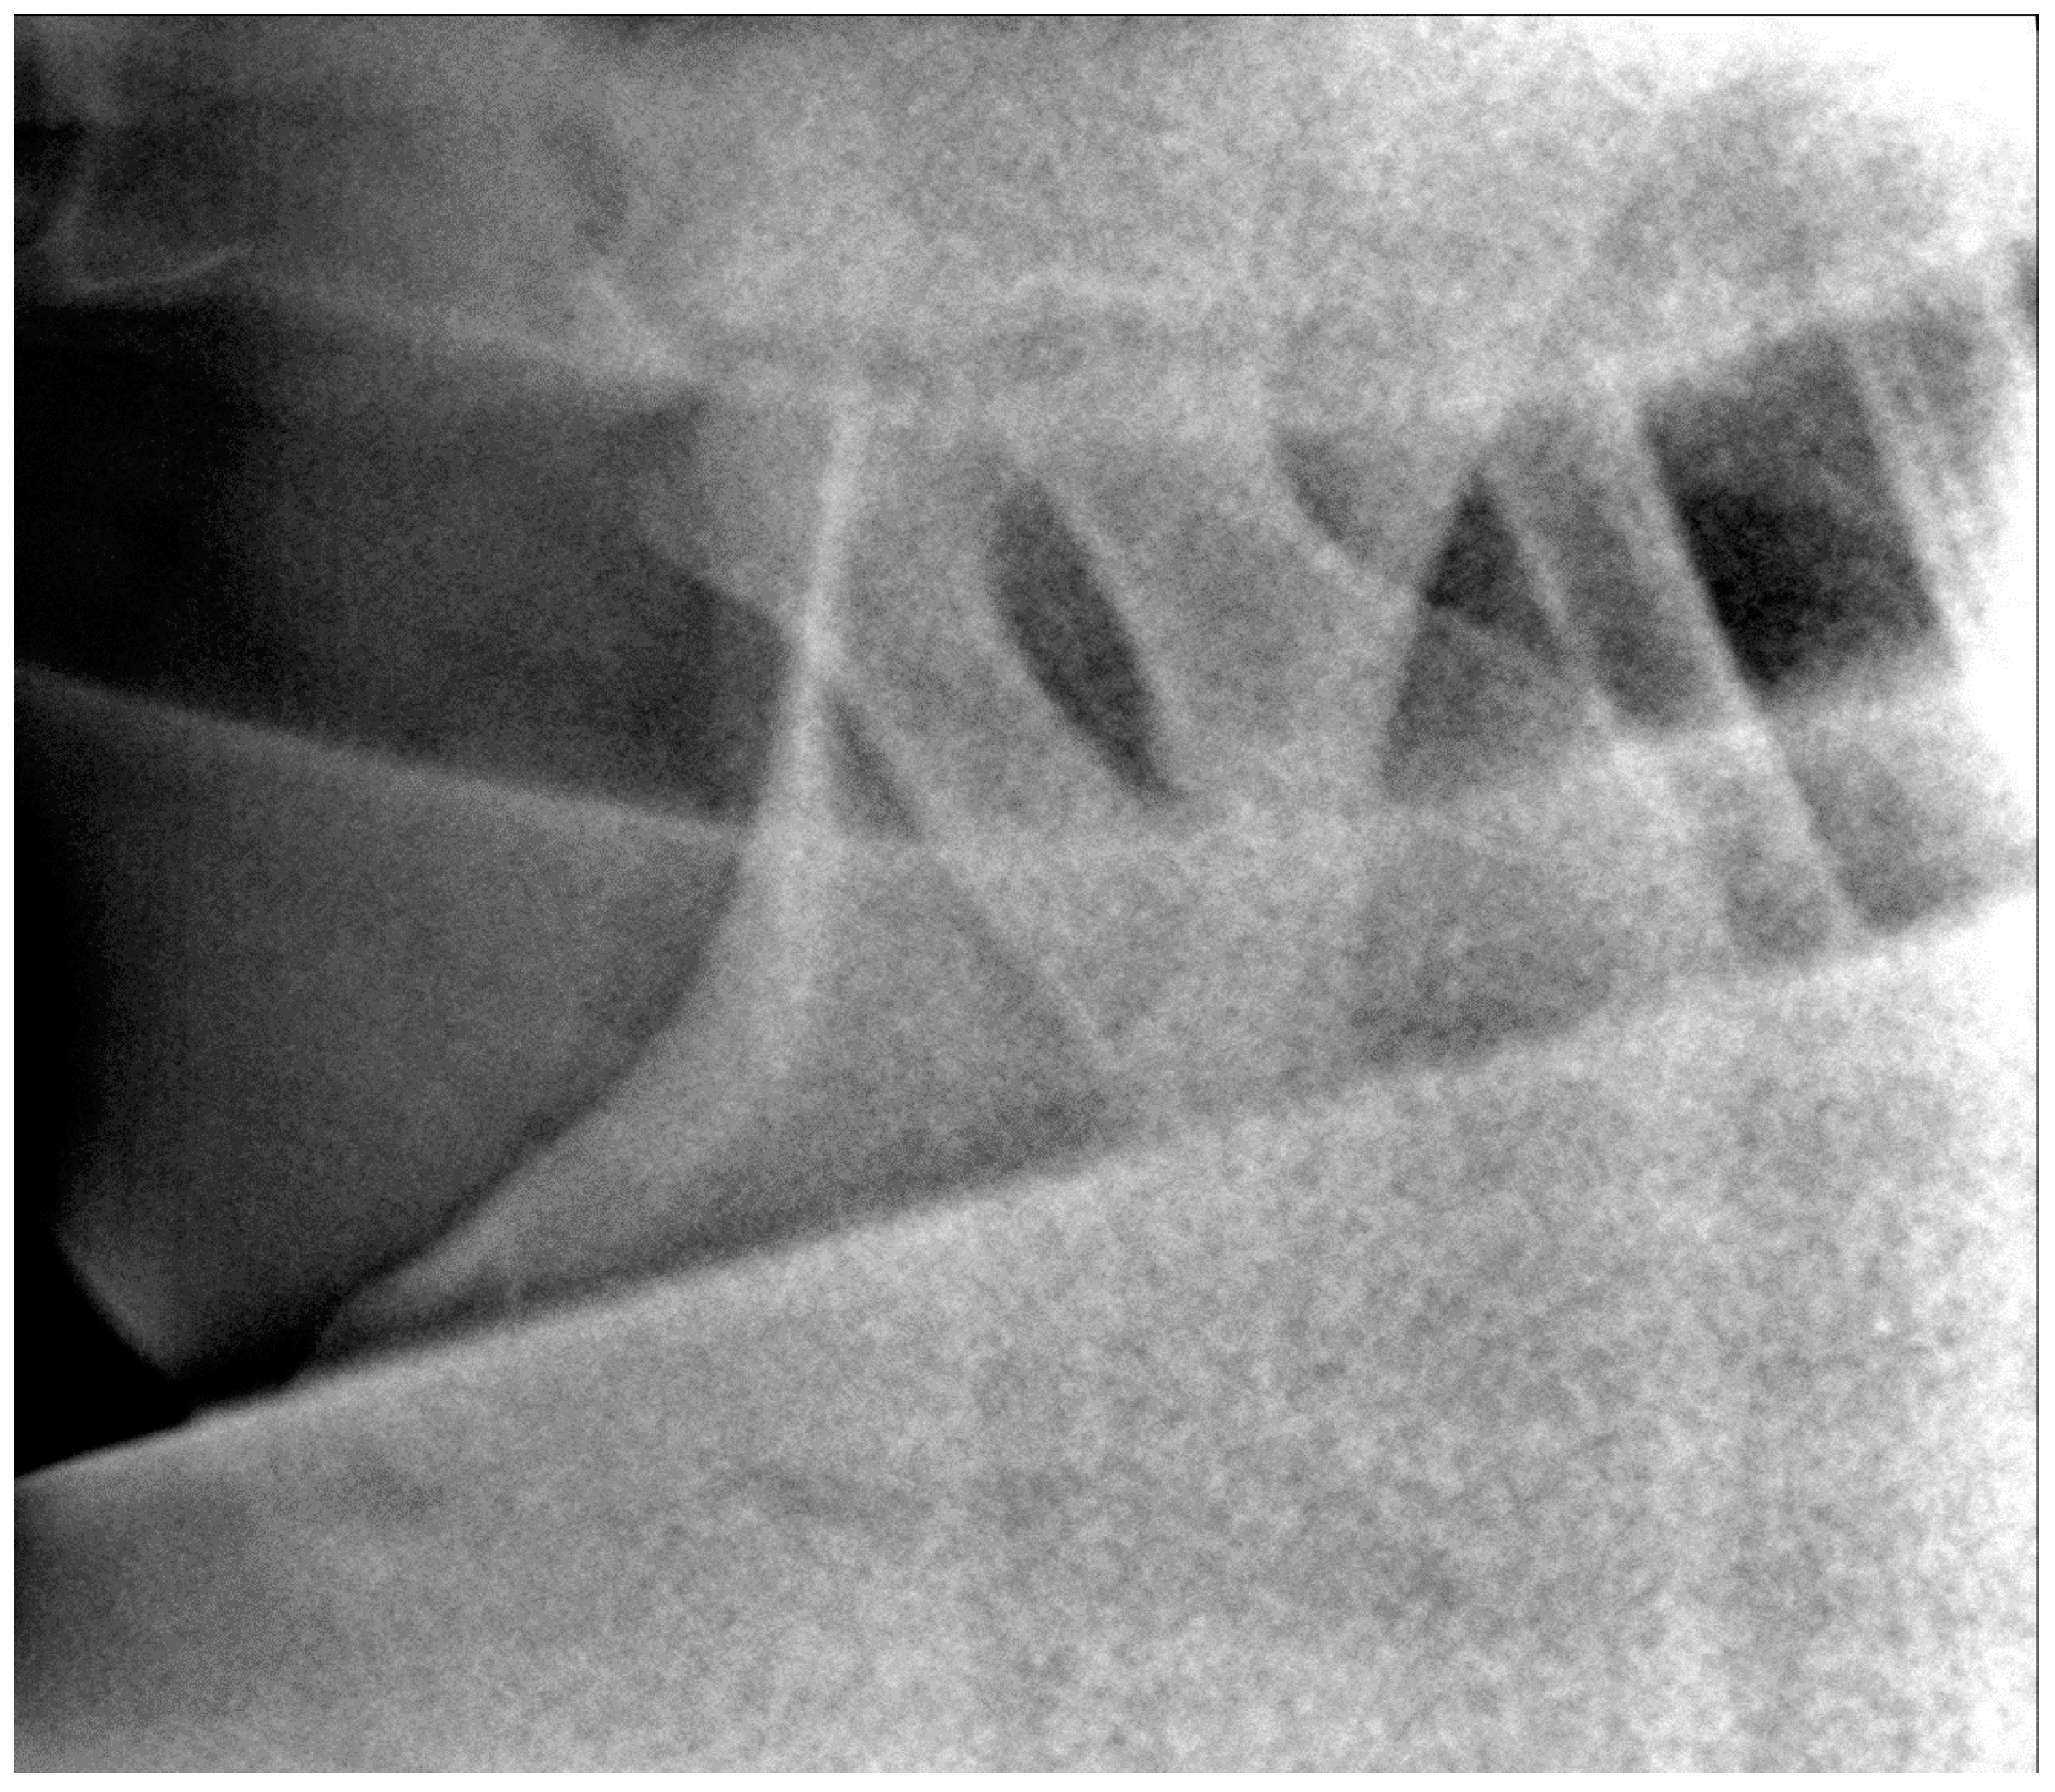

2.3. Radiographic Method

2.4. Classification System